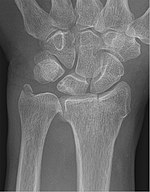

Chauffeur's fracture[4] Chauffeurs intra-articular fracture of radial styloid forced ulnar deviation of the wrist causing avulsion of the radial styloid Chauffeur's fracture Archived 2020-09-18 at the Wayback Machine at Wheeless' Textbook of Orthopaedics online Chauffeur-Fraktur und PSU bei Ulnavorschub mit Impaktation 83W - CR ap - 001.jpg